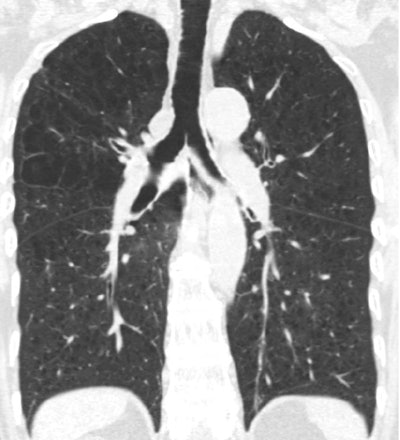

Measures of airflow obstruction have been associated with mortality; however, emphysema is defined as air-space dilation due to parenchymal destruction. And while emphysema can be defined on histology, in practice it is CT attenuation that defines the disease (< -950 HU in this study).

The research team examined 2,985 MESA participants ages 45 to 84 years who did not have airflow obstruction on spirometry. They defined emphysema-like lung as the number of lung voxels with attenuation less than -950 HU on cardiac CT after adjusting for the number of total imaged lung voxels.